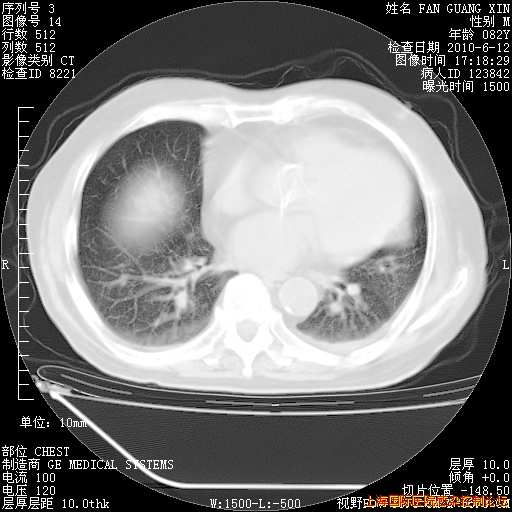

补发6月12日肺部CT肺窗

6月12日肺窗